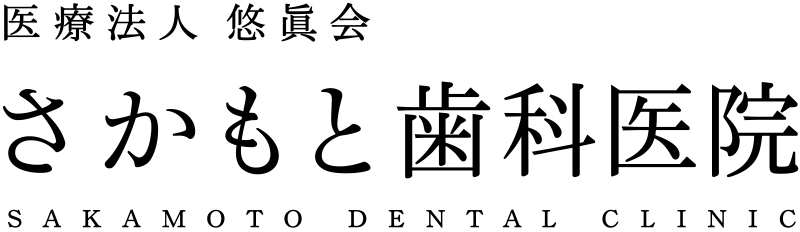

天然歯と

インプラント歯の違い

インプラント治療で取り戻した歯は、ほとんど天然歯と同じように見えますが構造に違いがあります。インプラントは、歯の根の代わりになる「インプラント本体」、歯の代わりになる「被せ物」、そしてその両方を繋ぐ「接合部」が合わさって人工の歯を作り直します。

インプラント治療の

主な方法

歯の根となる

インプラント体を埋入

歯の代わりになる

人工の歯のセット

埋め込んだインプラントを土台として、人工の歯を設置し、歯の見た目と機能を回復します。